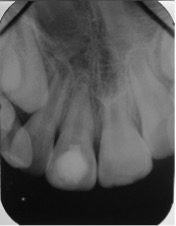

Se presenta el caso de un paciente de sexo femenino, de 8 años de edad. La paciente acudió acompañada con su padre al servicio de endodoncia del Instituto Nacional de Salud del Niño en Lima- Perú, con antecedentes de traumatismo dental, en sector antero superior y con dolor espontáneo. Al examen clínico intraoral, se evaluó que el diente 11 presentaba una ligera movilidad dental y al examen radiográfico se observó diente 11 no vital, ligero ensanchamiento del ligamento periodontal y desarrollo radicular en estadio 8 de Nolla (Figura 1 y 2). Se evaluó el caso y se realizó la explicación de las ventajas y desventajas del tratamiento de revascularización pulpar al padre de familia y se procedió a la firma del consentimiento informado para el tratamiento.

Figura 2: Radiografía periapical de diagnóstico.